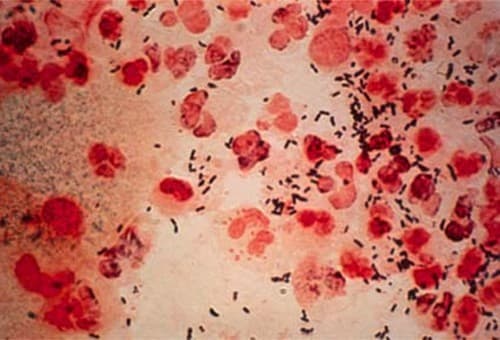

Lậu là một trong những lây truyền qua đường tình dục  nguyên nhân là do vi khuẩn gram âm Neisseria gonorrhoeae. Tình dục không an toàn là nguyên nhân chính dẫn tới bệnh lậu. Khi có dấu hiệu bệnh lậu người bệnh cần đi khám tại các cơ sở y tế uy tín để được xử trí sớm […]